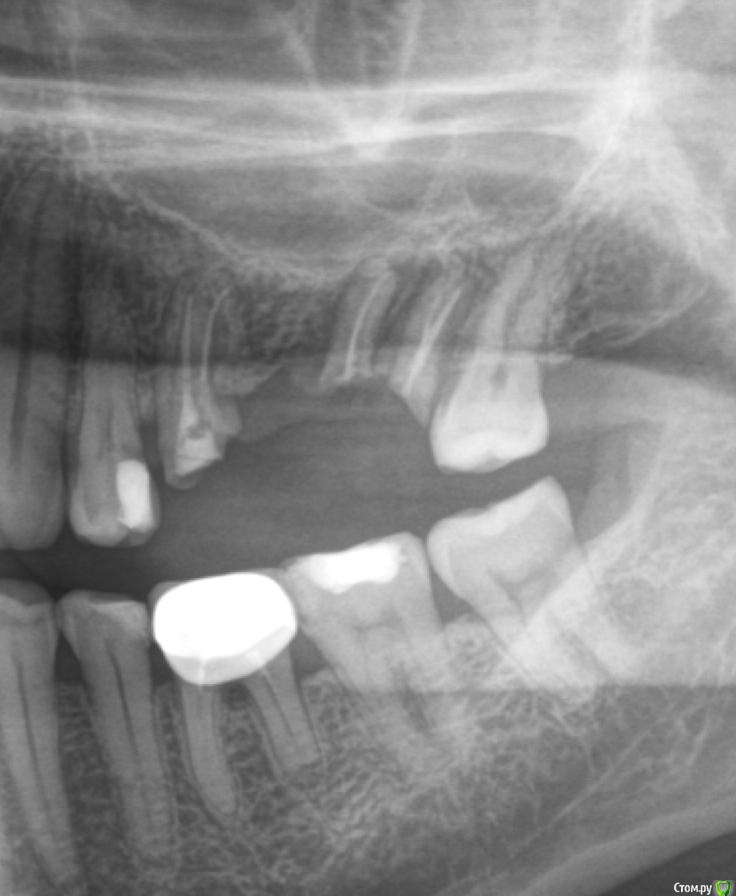

LTD Опубликовано 12 апреля, 2019 Поделиться Опубликовано 12 апреля, 2019 Мужчинка, 45 годов Слетел верхний мост 5-7 . Корень 7 (основание зуба ) отделился / разделился. «Целые» зубы 4, 8 не хочу трогать (обтачивать), решение зависит от бюджета. Просьба высказать мнение :а) Без имплантологии1 - делается ли вкладка на 7ку под дальнейший мост в таком состоянии? 2 - какие варианты восстановления возможны (съемные, бюгель и тд)?3 - какие варианты восстановления наиболее практичны по Вашему? б) хотя имплантация пока не по зубам Хочу понять:3 - на противоположной стороне 7-8 удачно стоит МК консоль на одном 7 зубе. Делается ли имплант с такой же конструкцией консоли на один 7-мой (который разрушен)?4 - делается ли одноэтапная имплантация на 7?5 - имеет ли смысл не удалять корни 7го с этой целью?6 - если 7 имплант + 567 мост (ставится ли мост - конструкция на 5й "свой") ?7 - возможность установки 7 без открытого лифта? Заранее спасибо! Ссылка на комментарий

chervoncevdaniil Опубликовано 12 апреля, 2019 Поделиться Опубликовано 12 апреля, 2019 7 удаление точно и в случае ее удаления установка 2х имплантология в позиции 6-7(если 5 удастся сохранить)Варианты со съёмным протезированием конечно возможны,но маловероятно что вы будете носить съемный протез на 2 зуба 6 Ссылка на комментарий

Doc Опубликовано 13 апреля, 2019 Поделиться Опубликовано 13 апреля, 2019 Копите деньги на имплантацию. Как накопите - семерку удалять и два имплантата. Если пятерка годная, то ее под коронку. Если нет, то удалять и все равно два имплантата, только мостом. Консоль здесь делать нельзя. Перегрузка слишком большая будет, потеряете имплантат. 1 Ссылка на комментарий

krokomot Опубликовано 13 апреля, 2019 Поделиться Опубликовано 13 апреля, 2019 Вот могут же пациенты, себя хорошо сфотографировать, что всё видно и понятно, присоединяюсь к коллегам, но нижний зуб под коронкой тоже от жил свое... 2 Ссылка на комментарий